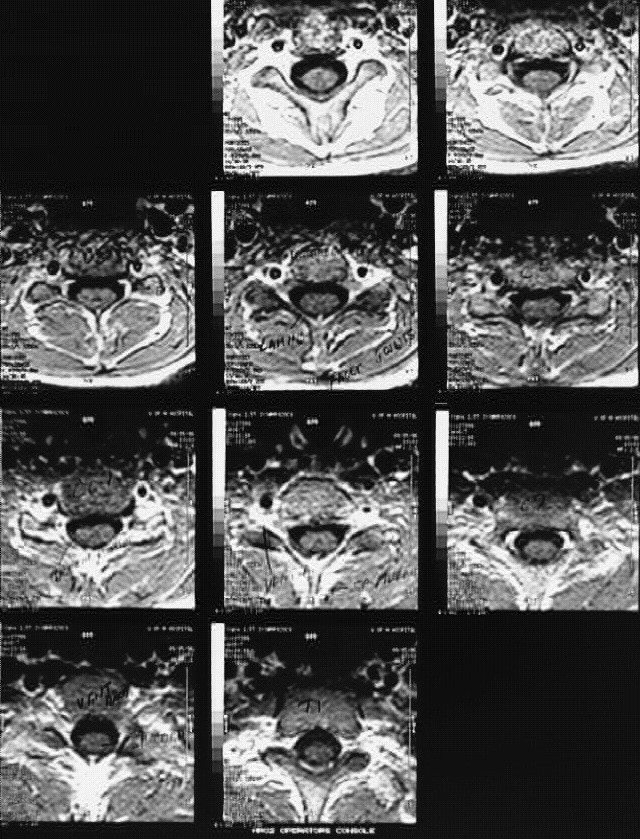

Radiology Images

Head & Neck: Cervical_Spine_MRI-Cross: